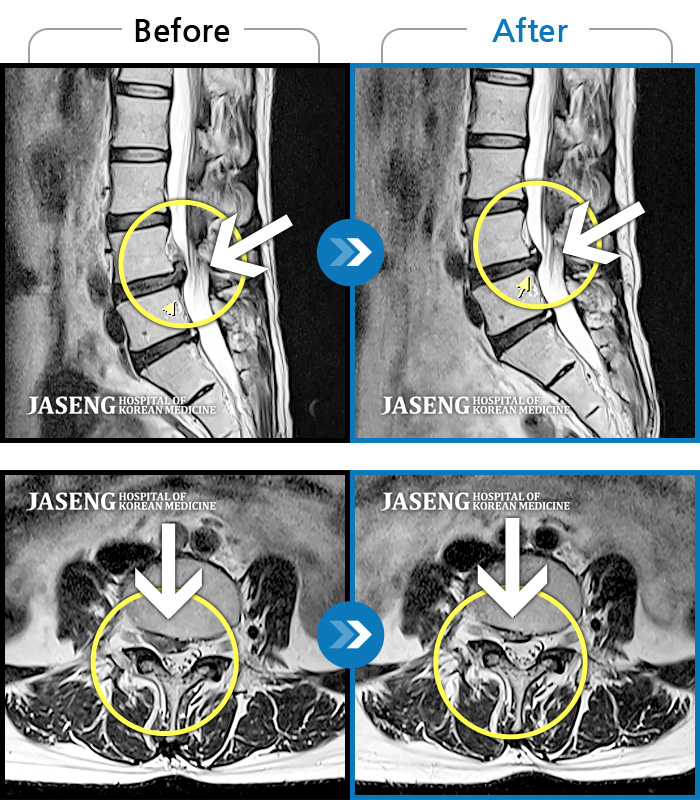

허리디스크

광주 · 이일석 원장

우측 허리부터 골반 통증, 우측 다리까지 이어지는 저림감, 10분이상 앉아있기 어려움

촬영시기

2023.12.15 ~ 2024.06.25

2024.07.09